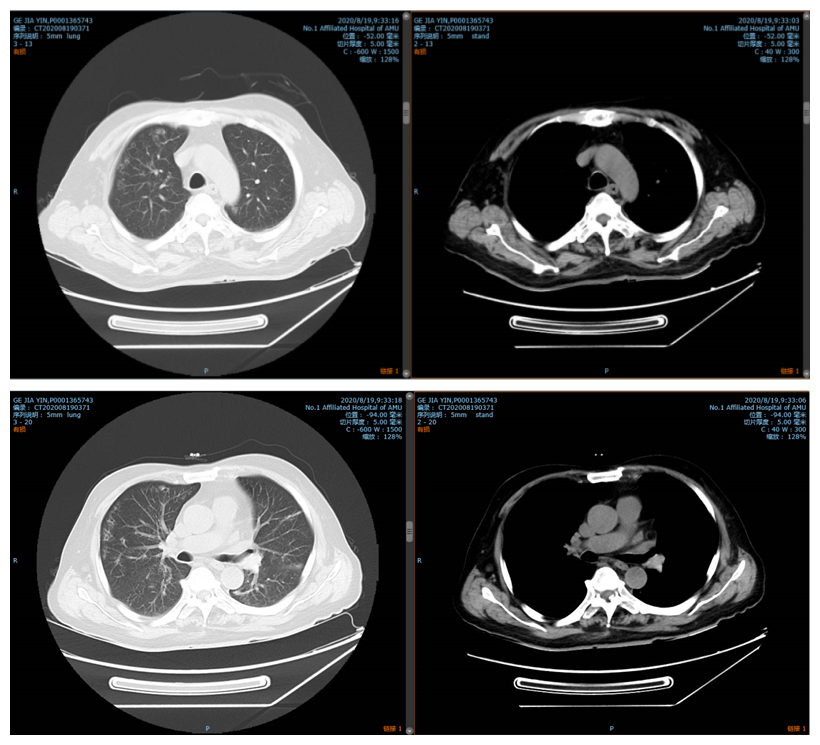

经科室讨论后,考虑患者目前重症肺炎诊断明确,且为废品回收人员,易合并多种病原体感染,遂调整抗生素为美罗培南、利奈唑胺联合伏立康唑加强抗感染,针对患者呼吸衰竭,积极予以无创呼吸机及高流量湿化治疗仪交替辅助通气,后患者体温逐渐降至正常,一般情况好转,复查胸部CT(图2)提示两肺病灶较前稍有吸收。

图2 患者治疗后好转CT表现